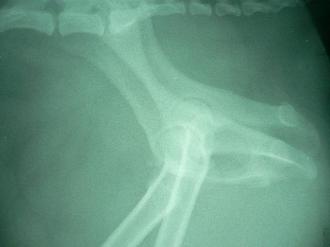

異常を察した飼い主さんは、急ぎ病院へ直行しました。身体検査では、かなりの痛みを感じます。股関節の解剖学的異常を感じ、早速レントゲン撮影に進みました。右の写真の通り患肢は後方へ脱臼していたのでした。